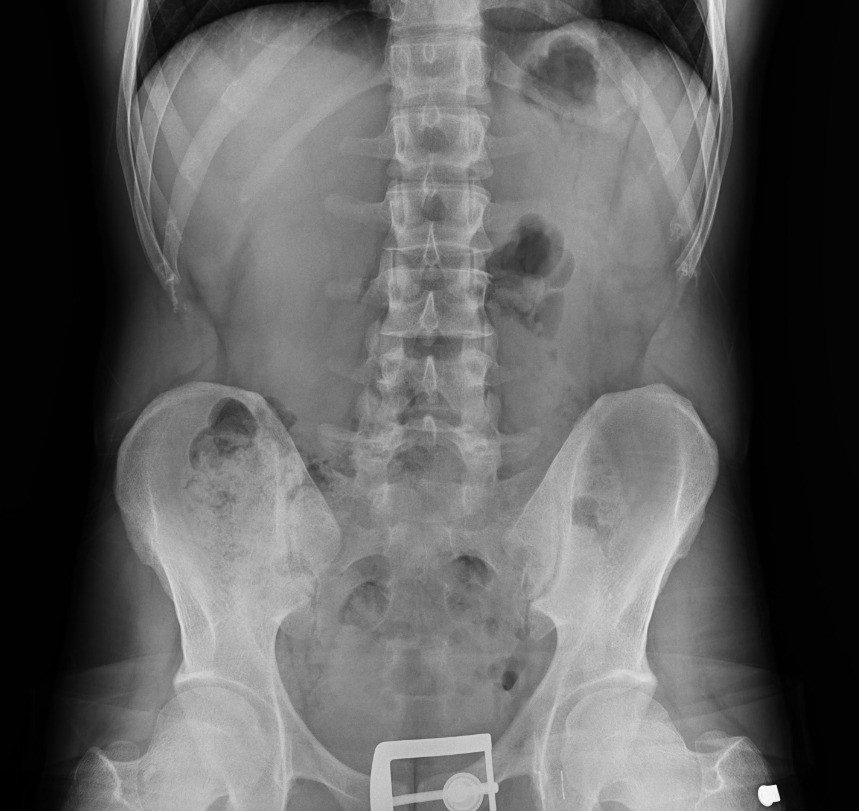

Diyarbakır’da 4 kişinin sindirim sisteminden 840 gram eroin ele geçirildi: 4 kişi tutuklandı

Diyarbakır'da şüpheli 4 kişinin sindirim sisteminden 121 parça halinde 840 gram eroin ele geçirildi.

Diyarbakır'da şüpheli 4 kişinin sindirim sisteminden 121 parça halinde 840 gram eroin ele geçirildi. Gözaltına alınan şüpheliler tutuklandı.

Araçta bulunan 4 şahsın ilk etapta yapılan kaba üst aramalarında herhangi bir suç unsuruna rastlanılmadı. Şahısların tedirgin haller sergilemesi ve rahatsızlık belirtisi vermeleri üzerine, adli makamlardan alınan karara istinaden yapılan tıbbi kontrollerde şüphelilerin vücut boşluğu/sindirim sisteminde 121 parça halinde 840 gram eroin ele geçirildi.